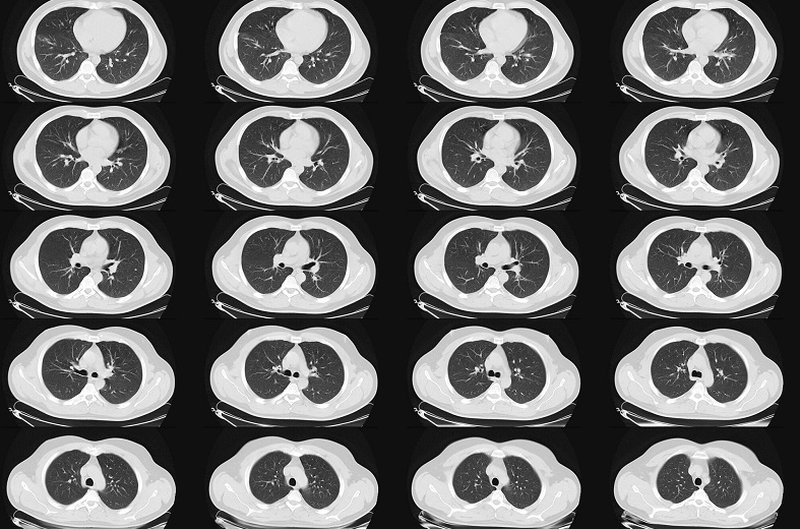

Nên chụp CT phổi vào lúc nào? Chụp CT phổi giá bao nhiêu?

Chụp CT phổi là phương pháp thu hình ảnh nhu mô phổi có độ phân giải cao để chẩn đoán chính xác các bệnh lý như ung thư, viêm phế quản… Vậy chụp CT phổi hết giá bao nhiêu và được chỉ định chụp khi nào?

Chụp CT phổi giúp phát hiện những tổn thương khó nhìn thấy trong phổi và là yêu cầu cần thiết trong chẩn đoán và điều trị bệnh về phổi. Vậy những trường hợp nào nên chụp CT phổi? Chụp CT phổi giá bao nhiêu? Bao lâu có kết quả? Hãy tham khảo bài viết sau để tìm hiểu các thông tin này nhé.

Nên chụp CT phổi vào lúc nào? Chụp CT phổi giá bao nhiêu? 1 Chụp CT phổi để bác sĩ đánh giá chính xác tình trạng tổn thương phổi

Nên chụp CT phổi vào lúc nào? Chụp CT phổi giá bao nhiêu? 2 Hình ảnh chụp CT cho phép phát hiện mức độ tổn thương phổi